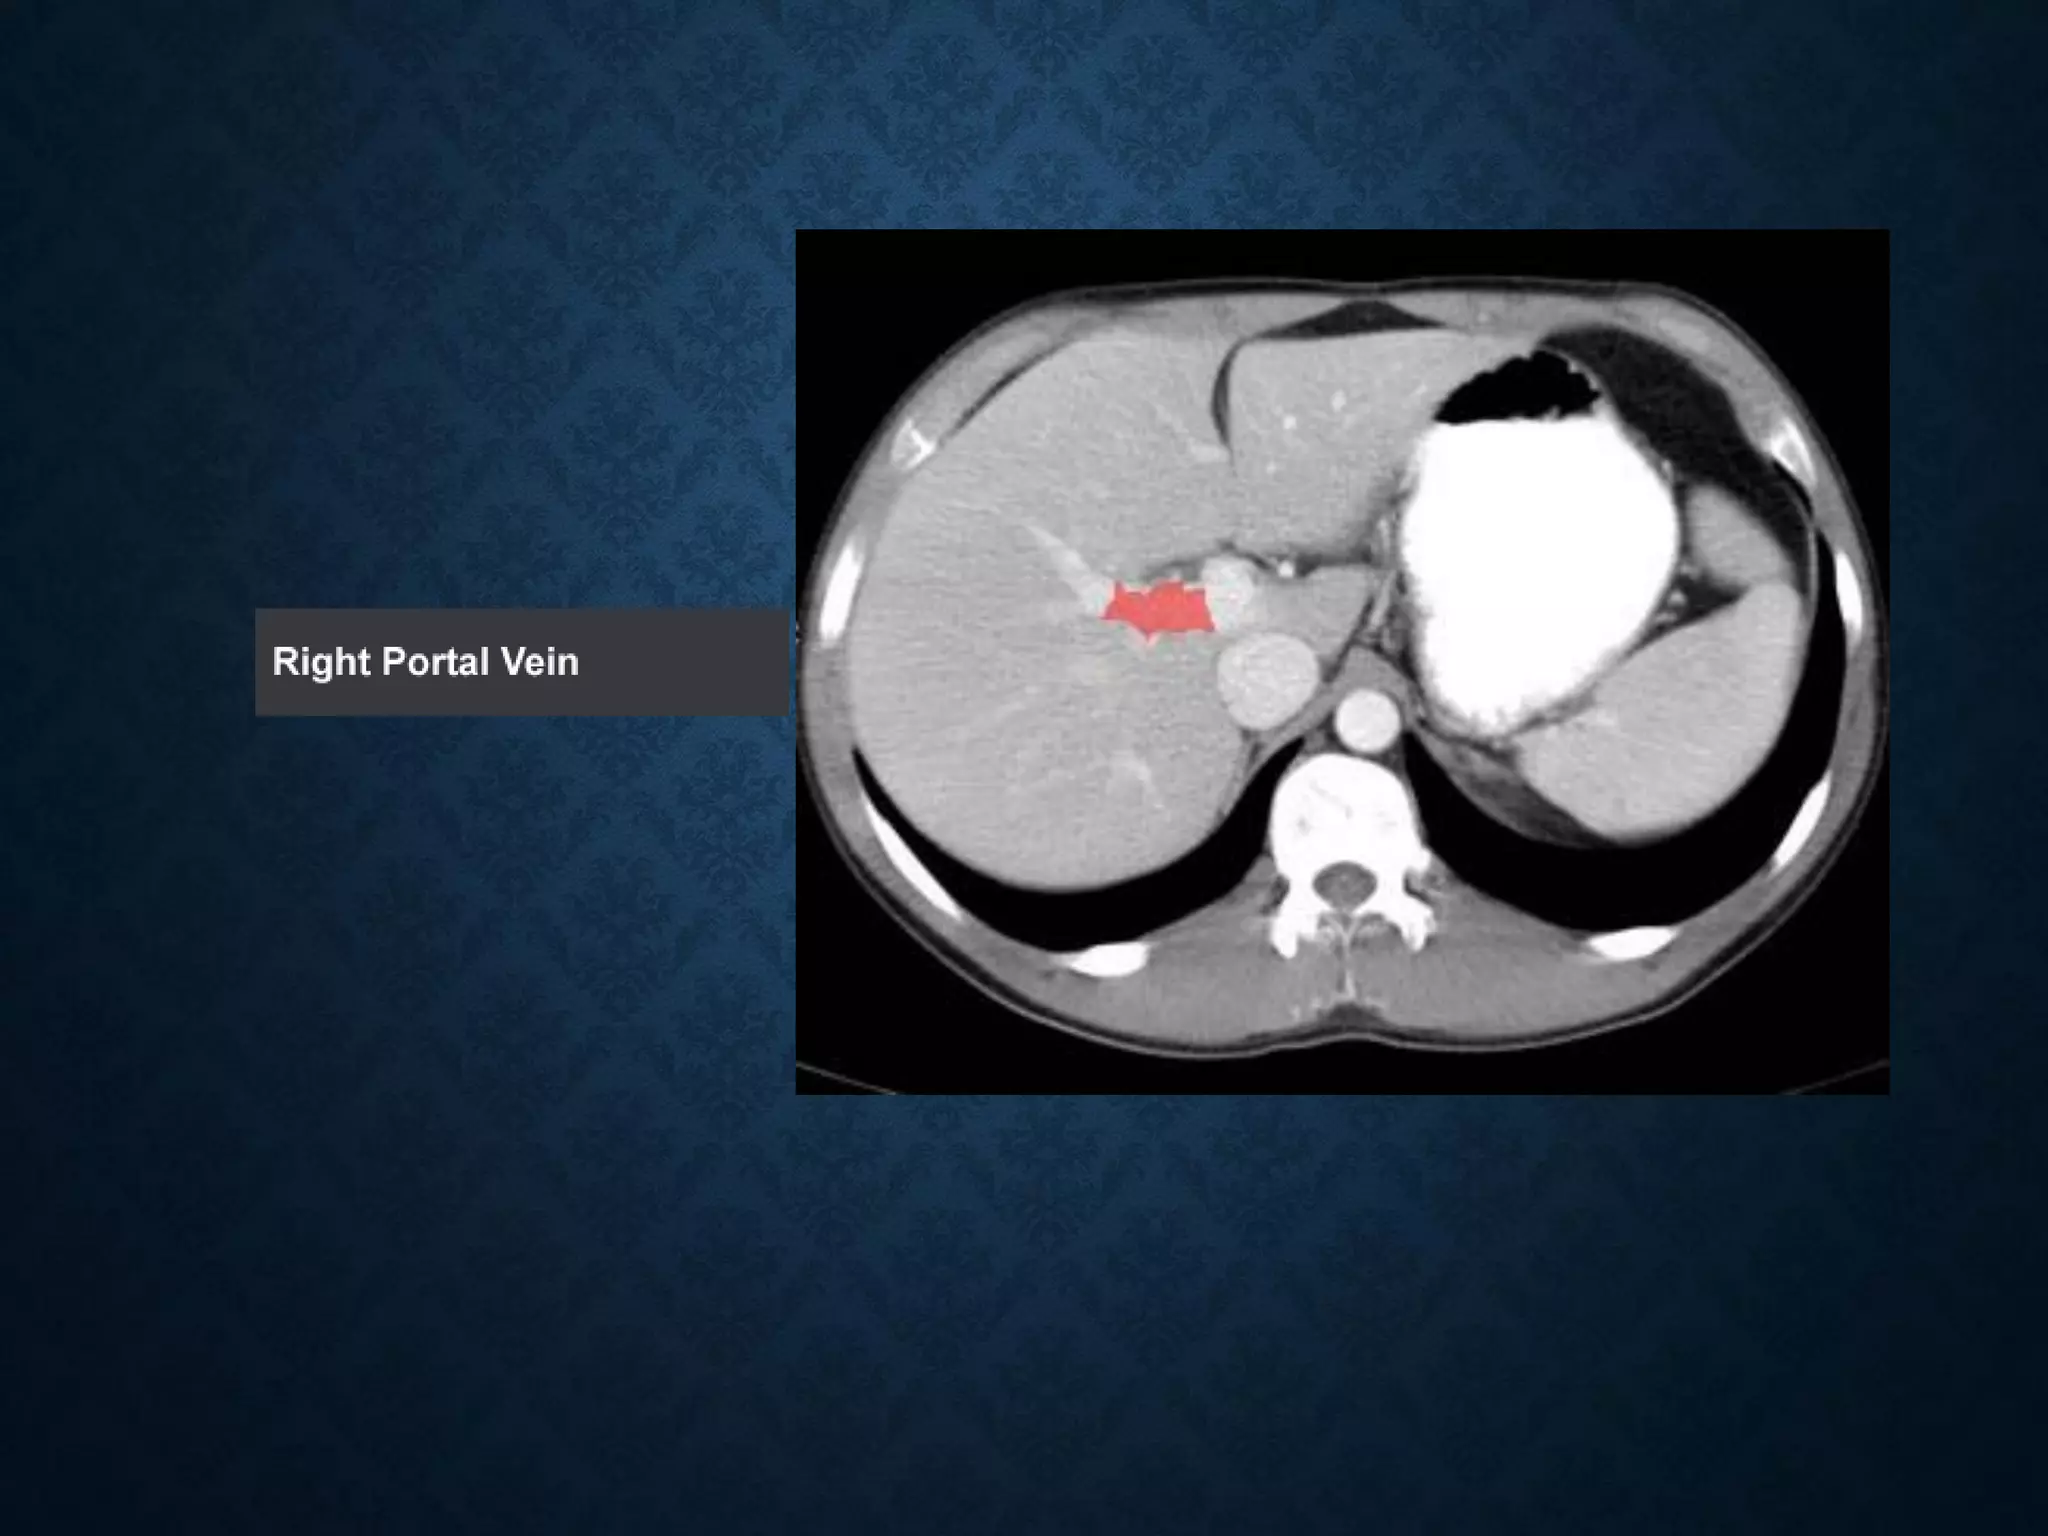

Identify the following structures in the body CT to the right. To view the location of the structure in the image click on

the label at the left and the structure will be indicated in the image. Abdominal CT scans typically begin just above

the diaphragm, so the first slice you see is of the lower chest.